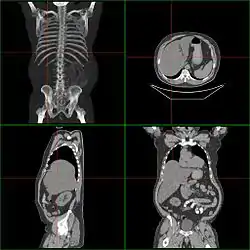

تصوير مقطعي محوسب ممكن أن يساعد في تحديد معلومات تشريحية دقيقة ولا تتأثر بالسمنة أو وجود غازات بالأمعاء.